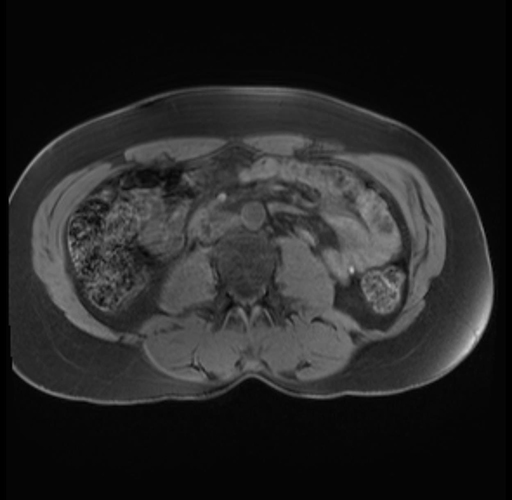

Imaging Analysis

Look through the patient's CT scan to identify any areas of concern for the necessary procedure.

Based on your CT findings, which issue(s) are present and would give reason for "planned slowing down moment(s)" in this case?